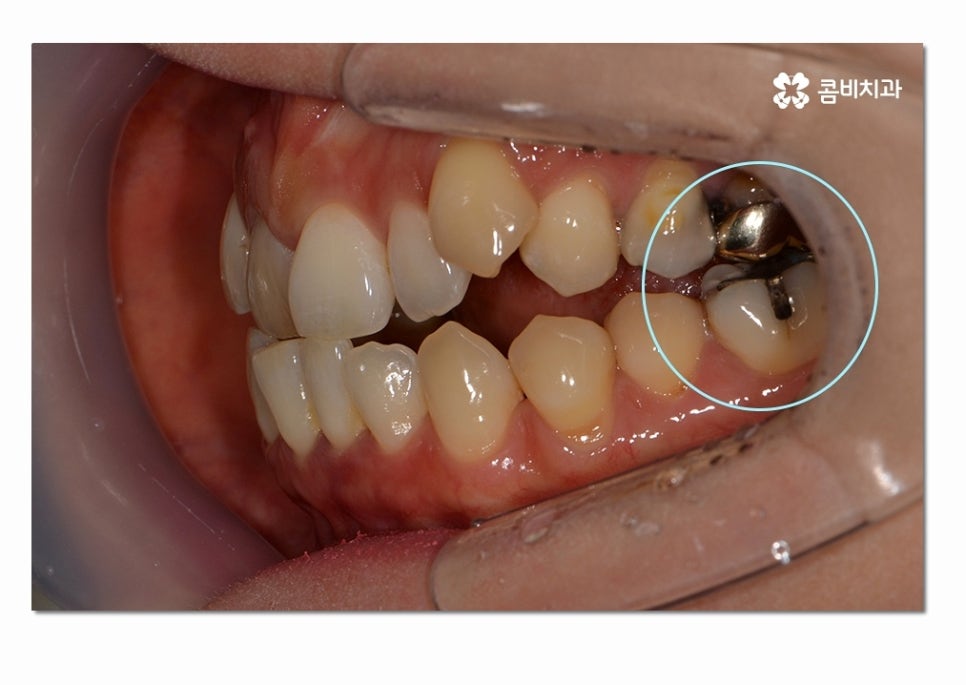

이렇게 옆면으로 보면 교합이 정상적으로 잘 맞물리지 않고

음식물을 골고루 씹어야 하는 어금니가 제대로

맞닿아 있지 않아서 불편함을 느끼게 될 수 있는데요.